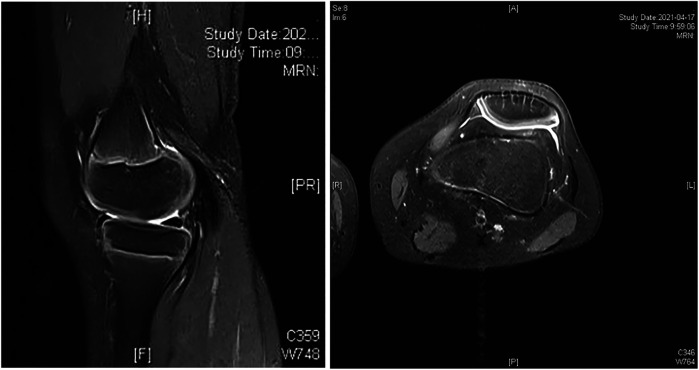

Abstract Image